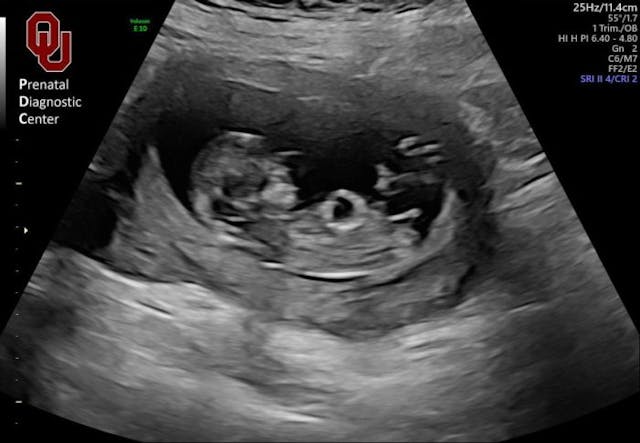

It was my 12-week appointment and I was so sure my second pregnancy was healthy, I glided into the ultrasound room full of jokes and smiles. Because I’m almost totally blind, I asked my husband, Austin, to describe the imaging, teasing him by asking which one of us Dallas looked like. But it turns out the life you expect for yourself can be taken away with something as simple as a knock at the door.

The next knock at the door was a maternal fetal medicine specialist whom we had not been scheduled to see. I put on a brave face, but as he explained the ultrasound results the world started to slip out from under me. There was a mass so large in my son’s abdomen that when Austin saw it on the screen, he thought it was his brain. Not only could no specialist diagnose it, none of them had ever seen anything like it.

All of this medical opinion was coming at me because of a picture of my son I couldn’t even see and now I had to wrestle with the fact that a useless photo of him might be all I ever had. Fear and grief were suffocating me, so in desperation I called the closest pregnancy resource center I could find, Hope Pregnancy Center of South Oklahoma City.